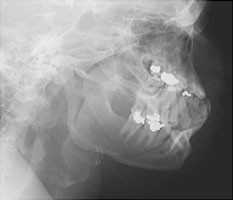

- Click on the image for a larger versionBLateral radiograph of the mandible. This is from the opposite side and redemonstrates the multiple fractures.